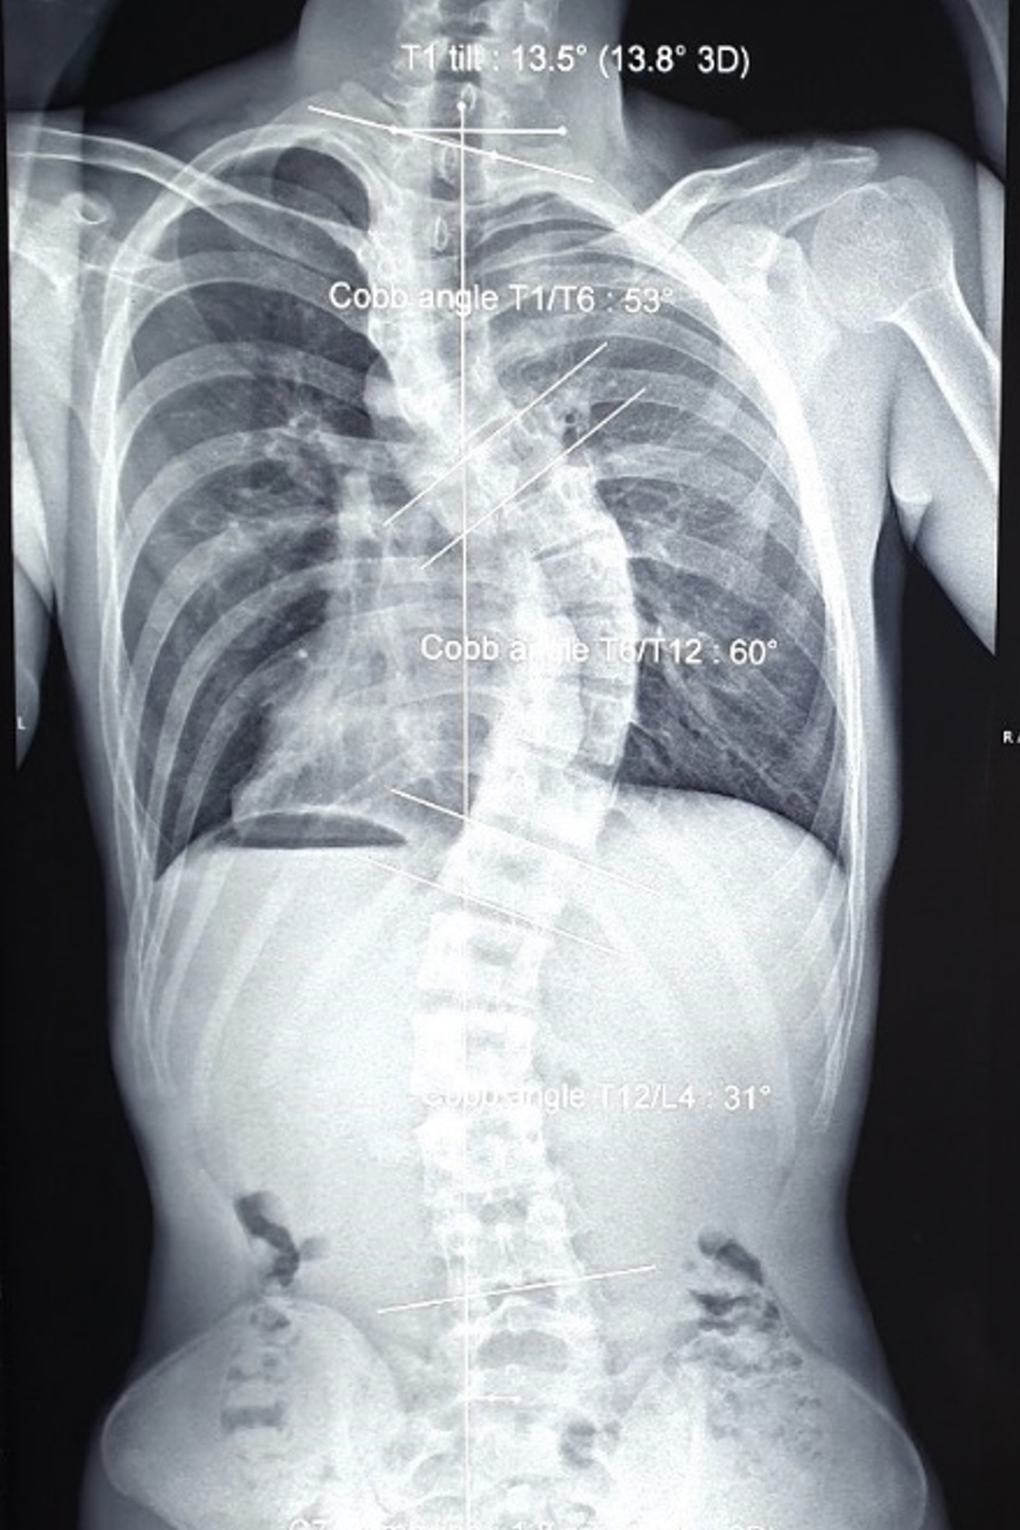

Nam sinh bị vẹo cột sống rất nặng, lồng ngực biến dạng (Ảnh: BS).

Vai trái Đ. lệch cao gần 5cm so với vai phải, lồng ngực biến dạng và lệch vẹo khung chậu. Ảnh chụp X-quang ghi nhận bệnh nhân bị vẹo cột sống đoạn ngực chữ S rất nặng.

Hình ảnh bệnh nhân bị vẹo cột sống đoạn ngực hình chữ S rất nặng (Ảnh: BS).